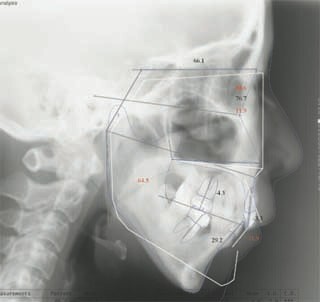

主訴:顎の歪み

診断名:骨格性下顎左方偏位

年齢:24歳

使用した主な装置名:TPB、マルチブラケット装置

抜歯/非抜歯および抜歯部位:非抜歯

治療期間:動的処置1年6か月、経過観察3年

費用の目安:保険適応 自己負担金として30~50万

リスク、副作用:外科手術によるリスク、マルチブラケット治療に伴う歯根吸収など偶発症が発生するリスクがある。

極めて強い側方変位を認めます。前後的・垂直的な問題は見られません。大きなズレであれば、外科的に骨のズレを改善する治療が選択されます。横断的な問題はその他の不正咬合と比較して、解決がかなり難しい事が多いです。治療後の後戻りが頻繁に見られる不正咬合ですので、外科矯正での改善が望ましい場合も多いでしょう。

このケースでは、外科手術は、上顎の傾斜の改善をLeFort1にて、下顎の正中の改善をSSROにて行いました。